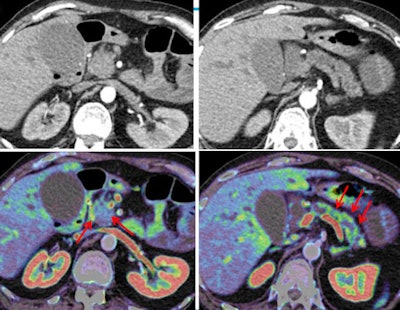

The same principle applies to the detection of tumors that are isodense to the surrounding parenchyma. These are difficult to detect even with multiphase CT, and often when they are missed "it basically means we picked the wrong phase," he said. "If you really know what you're looking for, you might be able to see something." Not so with CT perfusion, where the area shaded blue corresponds to the tumor, Prokop said.